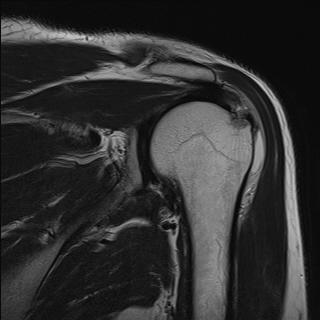

ÀÚ±â°ø¸í°Ë»ç

±Ø»ó°Ç ÆÄ¿­, Á¡¾×³¶¿°, °ßºÀÇÏ °ñ±Ø

¹æ»ç¼±»çÁøÀ̳ª ÀÚ±â°ø¸í°Ë»ç¿¡¼­ °ñ±ØÀÌ °üÂûµÇ°í ±Ø»ó°Ç ÆÄ¿­ÀÌ ÀÖ´Â °æ¿ì °Ë»ç¿¡¼­ º¸ÀÌ´Â

°ñ±ØÀÌ ±Ø»ç°ÇÆÄ¿­ÀÇ ¿øÀÎÀ̶ó°í ÃßÁ¤ÇÒ ¼öµµ ÀÖ´Ù.  ±×·¯³ª ±Ø»ó°ÇÆÄ¿­ÀÌ Ç¥Ãþº¸´Ù´Â ½ÉÃþ¿¡¼­

´õ ¸¹ÀÌ ¹ß»ýÇϰí Áõ»óÀ» ÀÏÀ¸Å°Áö ¾Ê´Â °ñ±ØÀÌ ¸¹Àº Á¡À» °í·ÁÇÒ ¶§ °Ë»ç¿¡¼­ º¸ÀÌ´Â °ñ±ØÀ»

Ä¡·á(°ßºÀ¼ºÇü¼ú)ÀÇ ´ë»óÀ¸·Î ÇÏ´Â °ÍÀº Çϸ®ÀûÀÎ °áÁ¤ÀÌ ¾Æ´Ï´Ù. ÀÌ È¯ÀÚÀÇ °æ¿ìó·³ ±Ø»ó°Ç

³»ÃøÀÇ ºÎÁ¾°ú Ç¥Ãþ ¶Ç´Â ÀüÃþ ÆÄ¿­ÀÌ ÀÖÀ¸¸é¼­ Á¡¾×³¶ÀÇ ºÎÁ¾°ú Ãæµ¹°Ë»ç ½Ã Ãæµ¹ ¼Ò°ßÀ» º¸ÀÌ´Â °æ¿ì¿¡

¹æ»ç¼±À̳ª ÀÚ±â°ø¸í°Ë»ç¿¡¼­ º¸ÀÌ´Â °ñ±ØÀÌ ±Ø»ó°Ç ÆÄ¿­ÀÇ ¿øÀÎÀ¸·Î ÃßÁ¤ÇÒ ¼ö ÀÖ´Ù.